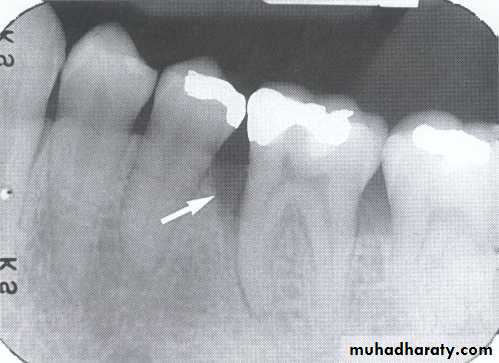

• B-Defective Restoration;

• Faulty dental restoration act as potential food traps & lead to the accumulation of food debris & bacteria.

• Radiographically; the defective filling identified with open or loose contacts, poor contour, uneven marginal ridges over-hangs.

Detection of Periodontal Disease

caries

Overhang rest.